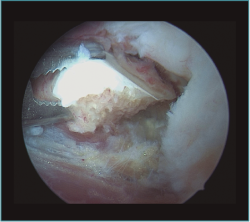

Figura 11. Caso 6. Visión artroscópica desde el portal anteromedial de la extracción del fragmento osteocondral inestable de la cabeza del radio.

Figura 12. Caso 6. Visión artroscópica desde el portal anteromedial tras la resección del fragmento inestable. Se aprecia el engrosamiento y enrojecimiento de la cápsula anterior.